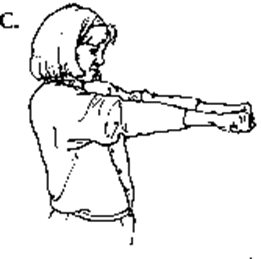

C. Make a tight fist with both hands.

Then bend both wrists down while keeping the fist. Hold for a count of 5.